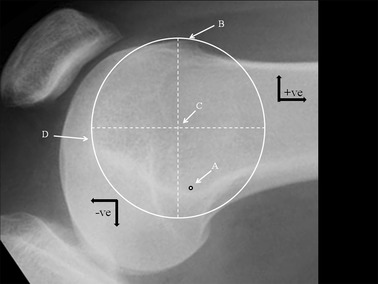

The radiographical analysis began by identifying the femoral tunnel position as defined by Schöttle [17] and marked ‘A’ (Fig. 1). Schöttle’s point lies just distal and anterior to a line drawn at right angles to an extension of the posterior femoral cortical line. The boss height was then measured [14], which is the distance between the extension of the anterior femoral cortical line and the right angle to the most anterior point of the groove. Using the ellipse tool available on the PACS program, and on the assumption that a dysplastic groove is an arc of a circle, a circle was created to match the groove. Circularity was confirmed by measuring and equalising the diameters at right angles. The centre of this circle was defined as the “isometric point” and marked ‘C’. The distance between A and C was measured and recorded. Using the anatomical axis (horizontal offset), the distance proximal (negative) and distal (positive) between A and C, and the right angle to this (vertical offset) were measured. The vertical offset was defined as positive if anterior and negative if posterior to the anatomical axis. No special scaling program was used to correct for any magnification errors and the results were measured in millimetres rounded to the nearest 0.5 mm. Two further measurements were taken, from point A to the most anterior point of the boss (B), and also from point A to the most distal point of the trochlea (D). The PFI cohort was further subdivided into those with a boss height < 5 mm and those whose boss height was ≥ 5 mm. A boss height of ≥ 5 mm has been defined as significant TD [6].

Lateral radiograph of the knee showing: A Schöttle’s point. B Most anterior point of the groove (also the point where the boss height is measured). C Isometric point (centre of the circle that includes the groove). D Most distal point of the groove. Black arrows indicate convention chosen for defining relative position of a point